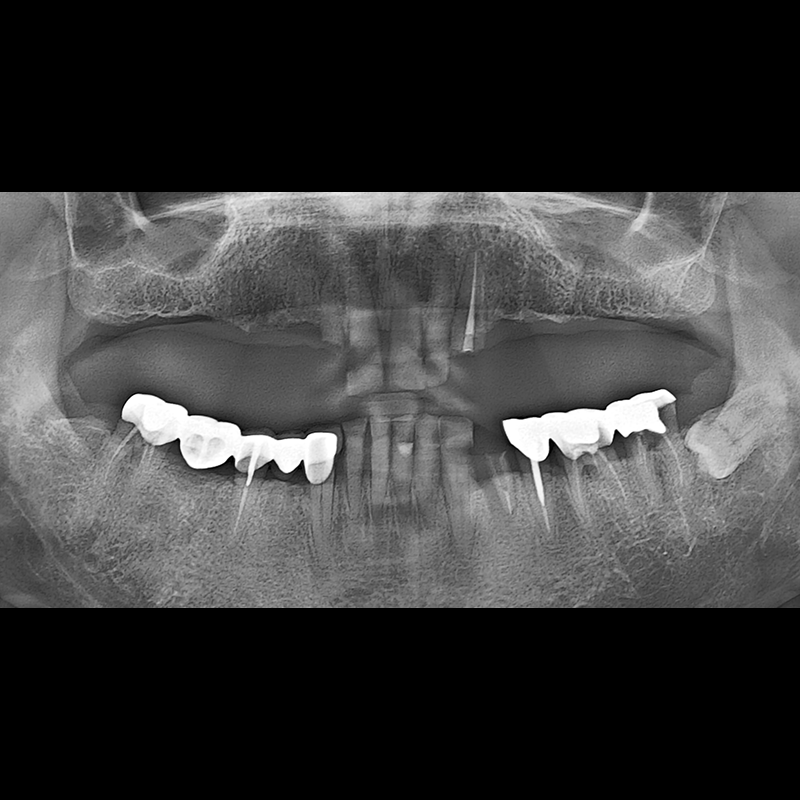

IMPLANT

BEFORE AFTER